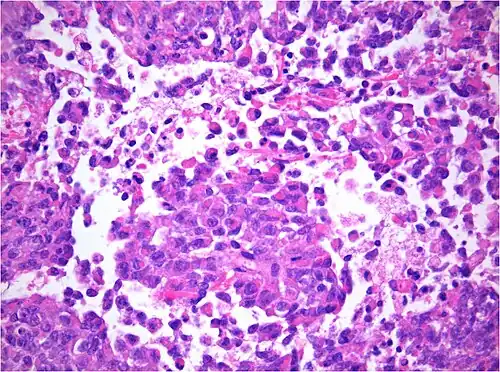

Pathology

AT/RT and rhabdoid tumor share the term "rhabdoid" because under a microscope, both tumors resemble rhabdomyosarcoma.

Histology

The tumor histopathology is jumbled small and large cells. The tissue of this tumor contains many different types of cells including the rhabdoid cells, large spindled cells, epithelial and mesenchymal cells, and areas resembling primitive neuroectodermal tumor (PNET). As much as 70% of the tumor may be made up of PNET-like cells. Ultrastructure characteristic whorls of intermediate filaments are seen in the rhabdoid tumors (as with rhabdoid tumors in any area of the body). Ho and associates found sickle-shaped embracing cells, previously unreported, in all of 11 cases of AT/RT.[24]